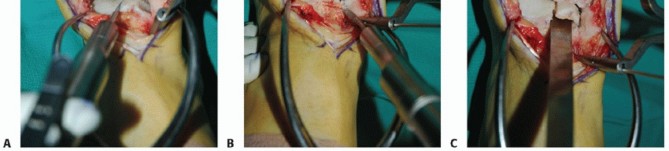

Anterior ankle arthrotomy (TECH FIG 1A)

Defines anterior joint margin for safe performance of medial malleolar osteotomy

Allows partial visualization of the OLT and allows confirmation that there is no diffuse articular cartilage degeneration

Open the posterior tibial tendon sheath-flexor retinaculum, directly on the posterior margin of the tibia and medial malleolus (TECH FIG 1B). Protect the posterior tibial tendon: It rests in a groove immediately posterior to the tibia and is at great risk with a medial malleolar osteotomy.

- TECH FIG 1 • A. Medial incision and anterior ankle arthrotomy. B. Opening of the posterior tibial tendon sheath. C. Predrilling of medial malleolus. Kirschner wire for trajectory of medial malleolar osteotomy has already been inserted and its position confirmed with fluoroscopy. D. Fluoroscopic image demonstrating Kirschner wire being used as a guide to direct the saw. E. The periosteum is scored perpendicular to the tibial shaft, at the level of the osteotomy. F. Medial malleolar osteotomy. Care must be taken to protect the posterior tibial tendon. (continued)

Predrill the medial malleolus across the proposed osteotomy site (TECH FIG 1C).

We routinely use two small fragment malleolar screws and predrill with the corresponding drill. Obtain fluoroscopic confirmation that the drill bits are in the proper trajectory.

Place a Kirschner wire obliquely to define the trajectory of the medial malleolar osteotomy (TECH FIG 1C).

Place it slightly proximal to the desired osteotomy so it can function as a guide but not interfere with the saw (TECH FIG 1D).

Confirm the optimal Kirschner wire trajectory with intraoperative fluoroscopy.